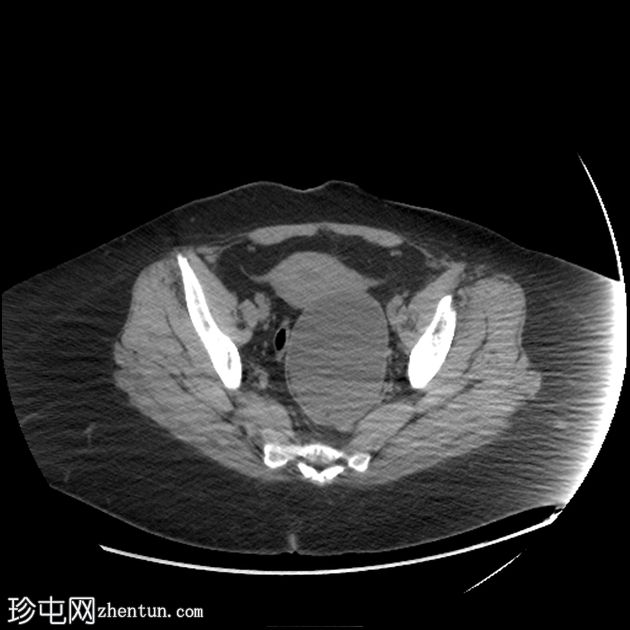

MRI

矢状位

T1加权像

盆腔可见部分囊性肿块,内含脂肪球。